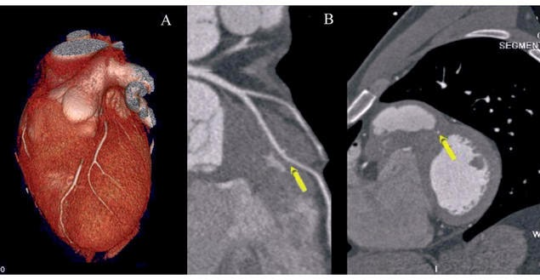

La Tomografía Axial Computarizada Cardíaca (TAC Cardiaca) emerge como una herramienta diagnóstica de inestimable valor en el vasto panorama de evaluaciones médicas disponibles. En un contexto donde la cardiología experimenta […]

El TAC (tomografía axial computarizada) es una prueba de diagnóstico que utiliza rayos X para crear imágenes detalladas del interior del cuerpo. Las imágenes de TAC se pueden utilizar para […]